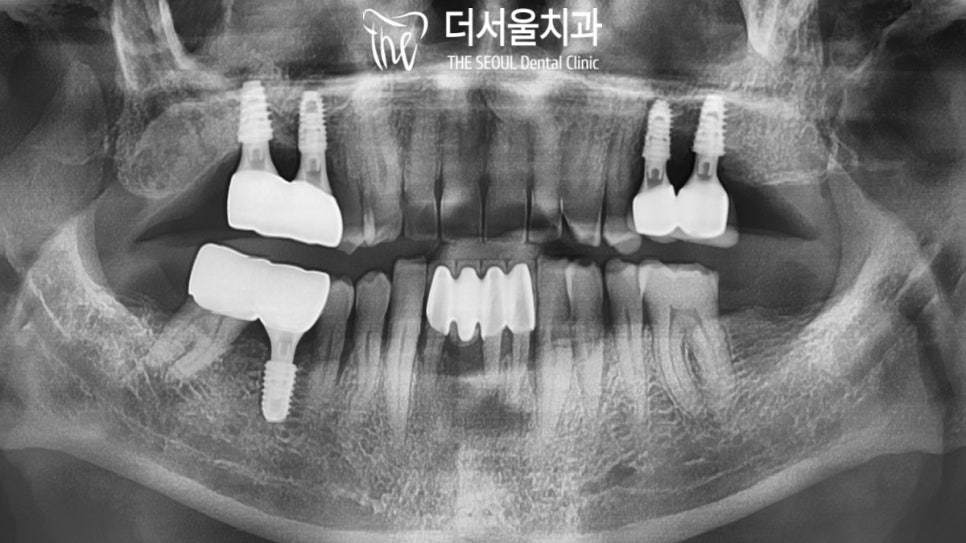

파노라마 사진을 찍어 확인해 봤더니

뼈가 너무 없네요..

# 16은 골소실이 너무 심해서

컴퓨터 모의수술 상에서도 무리인듯합니다.

뼈이식을 먼저 진행하여

모자란 골의 양을 채워준 뒤

상악동거상술 을 동반한

임플란트 를 진행하기로 했습니다.

4개월의 시간이 흘렀습니다.

오.. 이제는 뼈가 형성되었네요~

이제 계획했던 대로

상악동거상술 및 골이식을 진행하고

그 뒤로 임플란트 를 심어야 되겠네요.

여러 차례의 골이식을 통해

픽스처를 심어드렸으며

안정적으로 고정이 되어있는 것을

확인할 수 있었습니다.